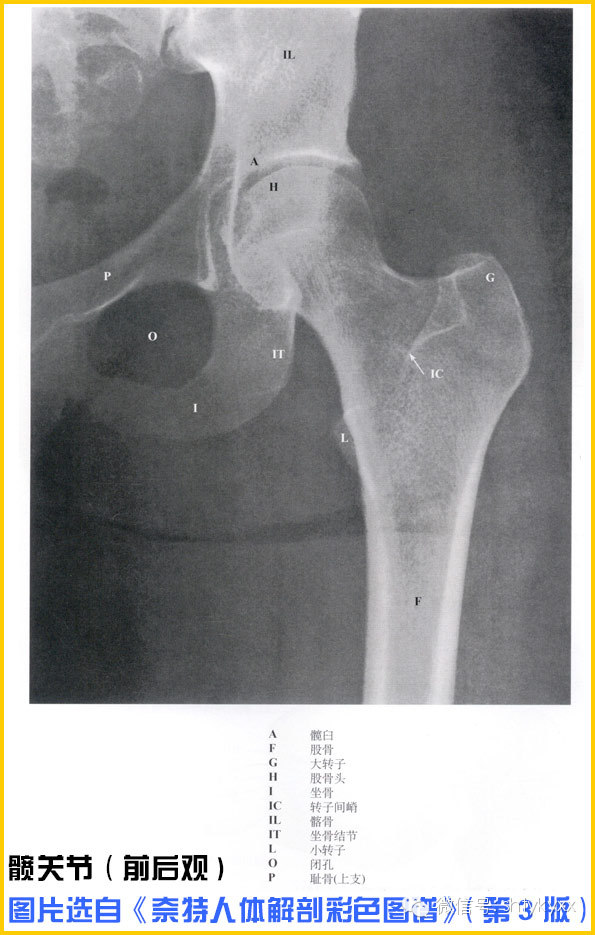

如果把人体比作是一台机器,那么肌肉和骨骼就是这台机器运转支架和发动机。从本期开始,平台将开通【一起学解剖】栏目,让小伙伴们在开始运动之前,真正的了解自己、认识自己!学习的教材选定了《奈特人体解剖彩色图谱》(第3版)和《Grant解剖学图谱》两本书。当然还是友情提示:知识有产权,阅读请购买原版书籍!

本期将我们将目光锁定在人体大腿和髋关节的肌群。骨盆可是人体最重要的动作枢纽之一,千万不要错过!